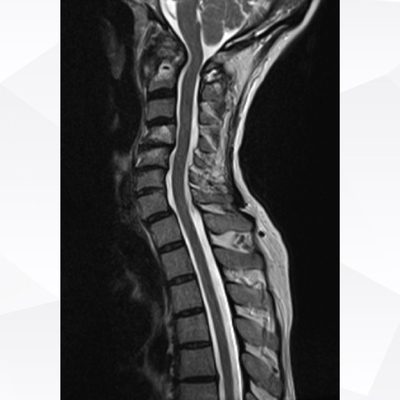

Click on an image below to view more info.